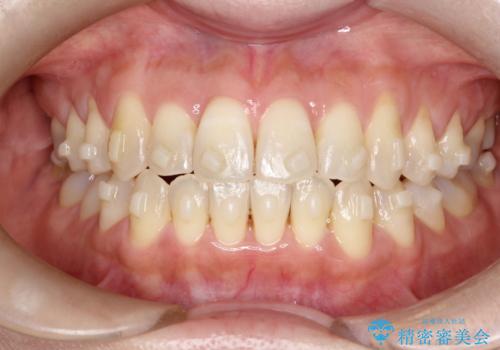

【開咬】笑った時の見た目を改善したい。

- 重度の開咬でしたがインビザラインで適切に治療計画を立て、きれいに仕上がりました。